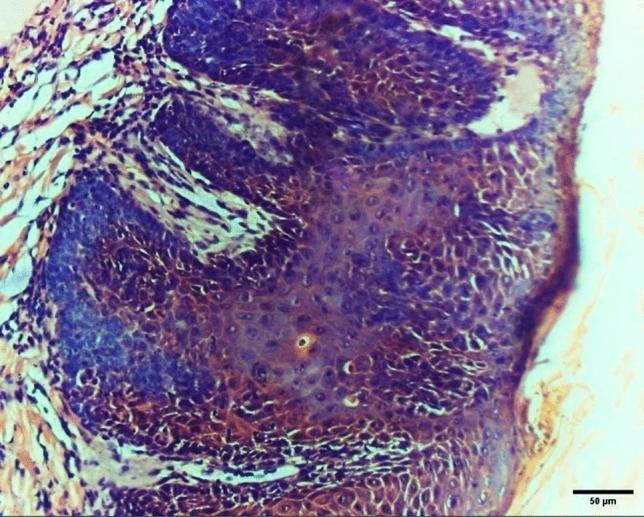

The treatment of oral squamous cell carcinoma (OSCC) includes systemic chemotherapy and is associated with aggressive side effects on patients. This study evaluated a new intra-tumor-targeted drug delivery method for the treatment of OSCC induced on the dorsum of the tongue in white mice. The induced tumors were examined by needle biopsy. A targeted anticancer drug (Cetuximab) and [Cisplatin and 5 Fluorouracil (5-FU)] chemotherapeutic agents were loaded on polyethylene glycol-polylactide-polyethylene glycol (PEG-PLA-PEG) nanoparticles (NPs) designed for intralesional injection while systemic administration was used as control. Fourier transform infrared spectroscopy (FTIR) was performed to study NP chemical structure, a drug release profile was conducted to study release kinetics, and histopathological evaluation was performed before and after treatment to evaluate tissue reactions (n-28, ά = 0.05). The drug release profile was characteristic of the chemotherapeutic agent showing early quick ascend followed by sustained slow release. FTIR peaks identified the polymeric structure of the drug nano-carrier. Histopathologic examination of chemically induced OSCC revealed different grades ranging from non-invasive to invasive stages of OSCC. Intra-tumoral test group revealed significant remission of observed cancer grade compared to the systemically administered group (X = 12.63, P < 0.001). Finally, using synthesized PEG-PLA-PEG NPs for intralesional injection is a promising route for the treatment of OSCC.